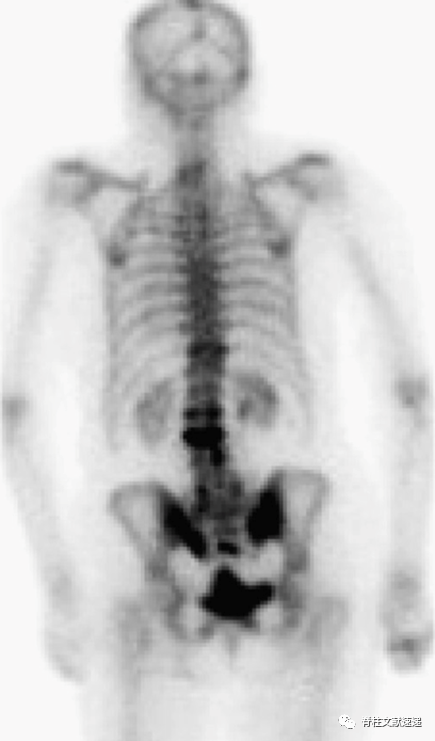

如下图所示,SPECT骨扫描显示双侧骶骨和 T11、L2 和 L3 椎体的摄取增加,提示骨折。